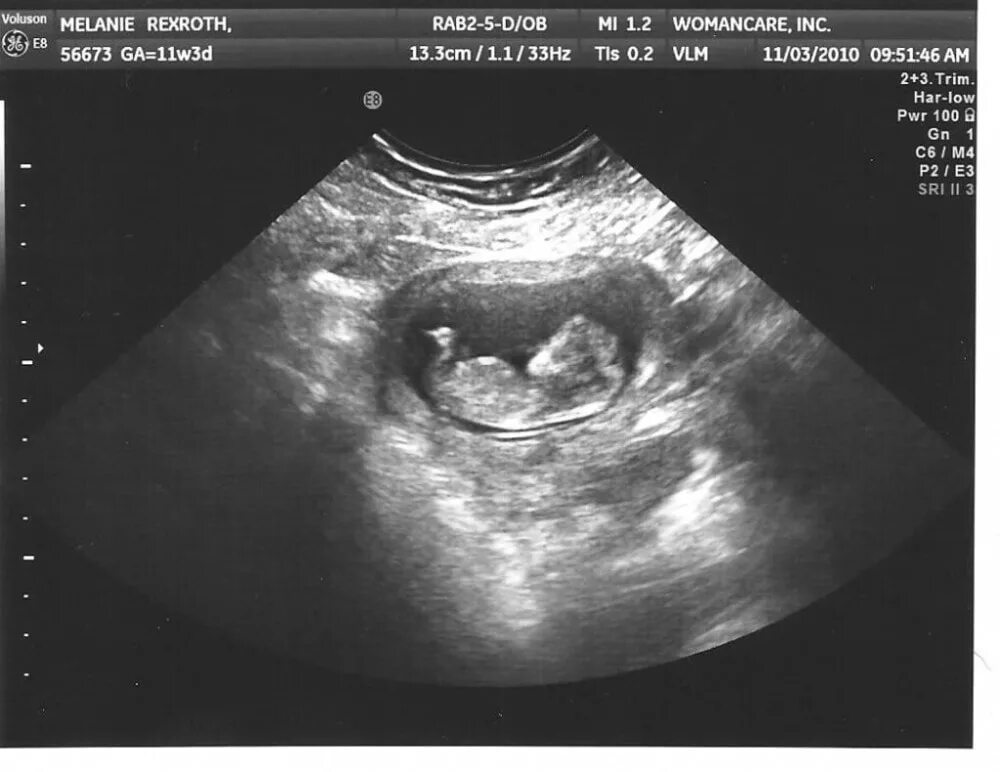

10 неделя беременности ощущения в животе